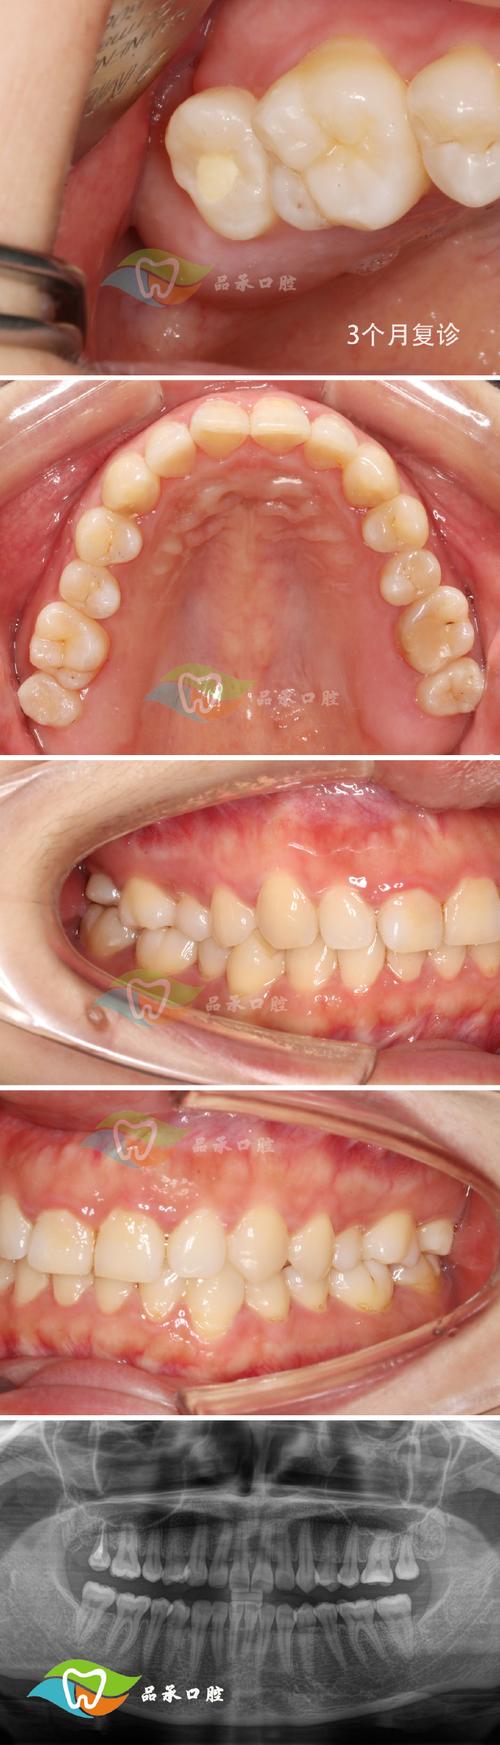

- GTR术后愈合期:

- 通常需要3-6个月甚至更长时间,让新骨充分形成和成熟,期间定期复查。

- 正畸治疗阶段:

- 在确认骨组织愈合稳定、牙周状况良好后开始。

- 关键: 施加轻柔、持续、间歇的矫治力,避免过大力量干扰新生骨组织,移动速度可能需要适当放慢。

- 正畸过程中需加强牙周维护,定期进行牙周专业洁治。